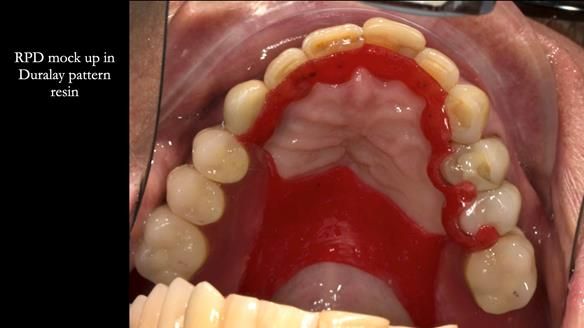

Instead, we made a Scandinavian-style, metal-based lower RPD.

It was made promptly, then relined gradually over the following year

to optimise fit, comfort, and support.

It’s worth saying that the lower denture in this case was made in the early days of Rowan and me using the Scandinavian approach. Rowan cast the metalwork himself for this denture.

Looking back, we would make this denture more hygienic now. The design and finish would be more refined and delicate, particularly when compared with the upper metalwork, which was made later using Chris Hesketh’s chrome work. I will discuss this in detail at the study club.

That said, the lower denture worked beautifully. It did exactly what it was meant to do, even though, by today’s standards, it looks a little agricultural.